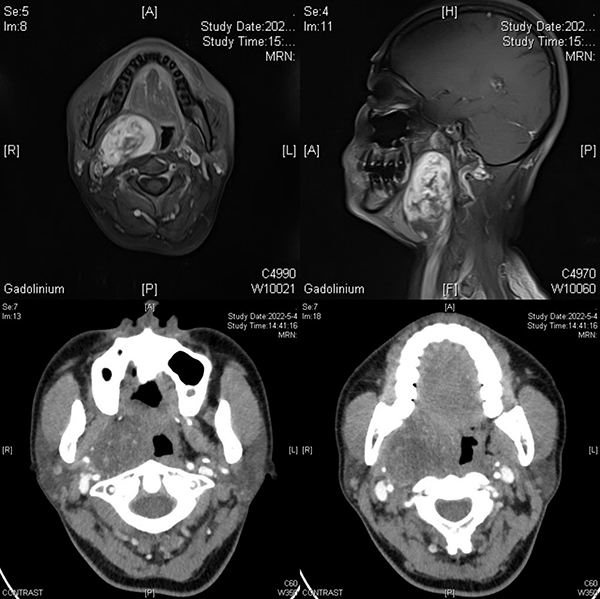

患者女性,47歲,因發(fā)現(xiàn)右頜下區(qū)腫物6年入住徐醫(yī)附院口腔頜面外科。入院后經(jīng)過(guò)頜面部增強(qiáng)CT和增強(qiáng)MRI檢查發(fā)現(xiàn)患者為右側(cè)口咽部腫物,腫物體積較大,上達(dá)顱底翼外肌水平,下至甲狀軟骨水平,致使半側(cè)咽腔堵塞。李家鋒主任憑借影像學(xué)資料及多年的臨床經(jīng)驗(yàn),初步考慮為神經(jīng)鞘瘤可能。但由于腫物體積較大,位于咽側(cè)深區(qū),毗鄰頸部重要大血管,致使該手術(shù)具有較大的難度和風(fēng)險(xiǎn)。既往對(duì)于該類型腫瘤,由于腫物體積較大,為避免重要血管及神經(jīng)損傷,術(shù)中需暫時(shí)劈開(kāi)下頜骨暴露腫物實(shí)施手術(shù)。術(shù)前和患者及其家屬溝通后,患者對(duì)下頜骨暫時(shí)劈開(kāi)心理負(fù)擔(dān)很大,希望盡可能避免下頜骨的劈開(kāi)。